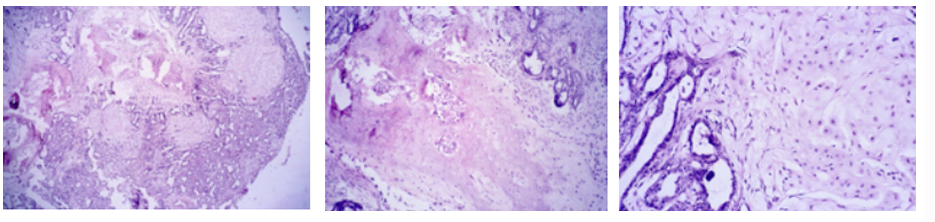

Vasculitis chronica (Mediocalcinosis- H&E staining)

Description: Thicker tunica media of aorta. Consists of native fibrous tissue which proliferates. Evidence is the increased number of fibroblasts with production of intercellular collagen fibers. Infiltration by lymphocytes and macrophages can also be observed, showing a chronic inflammatory process in the blood vessel wall.

Etiology: Characteristic of uremic syndrome in dogs. Can be caused by infectious agents, immune-mediated mechanisms or as a result of inflammatory processes in adjacent vessels.

Pathogenesis: An inflammation of blood vessels. Developed by complex mechanisms which depend on causative agents. The immune system mistakes components of vessel walls as foreign and attacks them with immune cells. Continuous inflammation leads to damages and thickening of the wall, narrowing the lumen and sometimes blockage which compromise the blood flow.

this is?

Mediocalcinosis (van Koss)

Description: Same as 261, stained with Van Koss to prove deposition of calcium (dark brown staining). Between t.intima and t.media among the cells, there is also observed brown diffuse staining in intercellular mass.